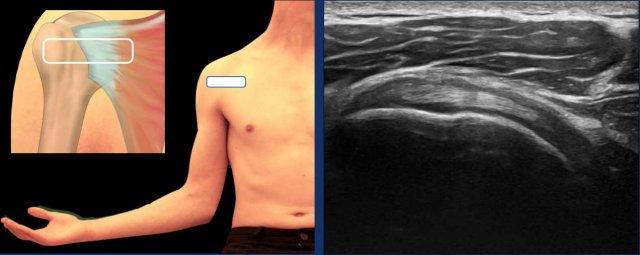

Vị trí tối ưu để khảo sát gân cơ trên gai là tư thế Crass cải tiến. Ở tư thế này, bệnh nhân được hướng dẫn đặt tay lên hông cùng bên hoặc hướng về túi quần phía sau (xem hình).

Một lựa chọn thay thế là tư thế Crass, trong đó bệnh nhân đặt cánh tay ở tư thế xoay trong ra sau lưng.